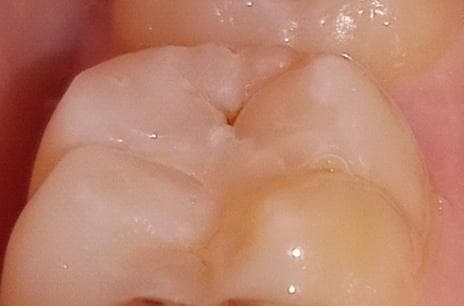

(첫번째 사진은 레진하고 며칠뒤에 찍은 사진이고

보통 레진할 때 충치부위 제거하고 레진으로 덮지 않나요?

글규 첨에 레진하고 거울 보니 저렇게 구멍난 부분이 있어서.. 며칠 뒤에 여쭤보니 활동멈춘 충치라고 제외하고 나머자 부분 해주셨다고..그러셨는데.. 저것도 그렇고.... ( 처음부터 말씀해주셨으면 레진안하고 경과 지켜봤을 텐데.. 전혀 아프지도 않았는데..)

제가 궁금한 부분은 레진 벗겨진 곳에 갈색 자국이 있어도 되는건가요? 저것도 정지우식이라서 그냥 레진으로 덮으신걸까요?